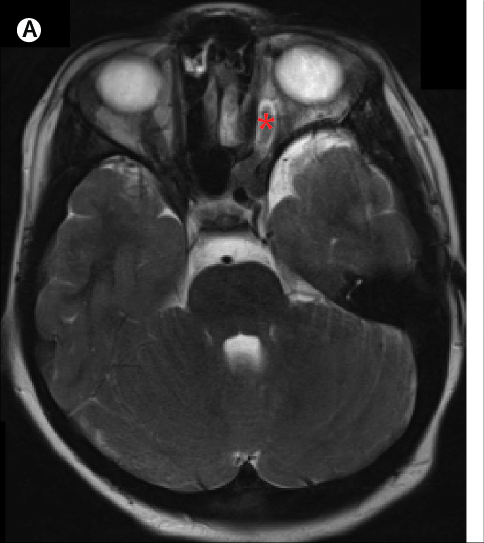

去到医院后做进一步检查发现,怡怡的颅内肿瘤长在两侧视神经交叉的部位上,这种肿瘤学名叫【视神经胶质瘤】,这是一种良性肿瘤,如果能全切就能达到治愈的目的,但是全切谈何容易。

视神经胶质瘤是发生在视神经内胶质细胞的良性肿瘤,多发于学龄前儿童,这个病最典型最早期的表现就是视力下降,但由于患儿年龄较小,不太会表达,以至于家长没有注意到孩子的异常,最后延误了病情。当肿瘤越来越大的时候,孩子会有眼球突出、视盘水肿、眼底出血等症状,家长这才觉得不对劲,这时手术的话具有一定的风险,可能会损害视神经导致孩子全盲。所以各位家长要警惕孩子的异常行为和语言,不止视神经胶质瘤,任何疾病在早期的预后都比中晚期好。